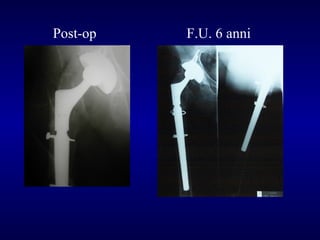

Paprosky 1

Post-op

F.U. 6 anni